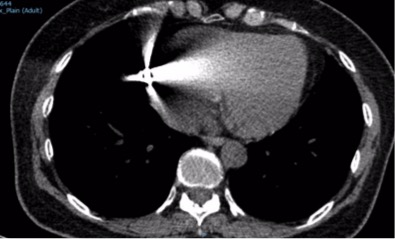

Dị vật cản quang ở nhĩ trái trên phim MSCT

cản quang. Sau khi hội chẩn, các bác sĩ quyết định chụp MSCT không cản quang

cho người bệnh để xác định vị trí của dị vật. Sau khi phân tích kết quả chụp,

kết luận được dị vật nằm trong nhĩ phải. Sau khi hội chẩn và bàn bạc cùng gia